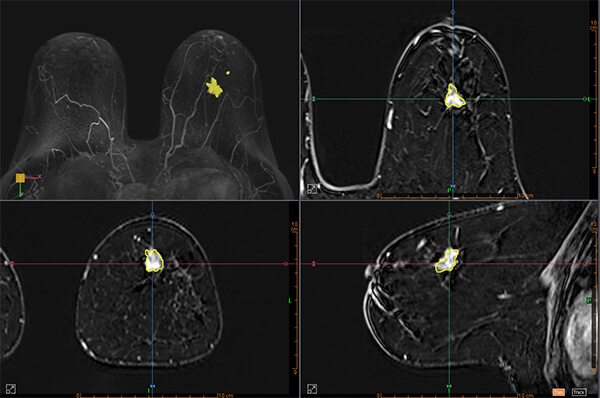

- Εφαρμόζεται στο τμήμα μας από εξειδικευμένους ιατρούς*, με τη χρήση ειδικών τεχνικών πολυπαραμετρικής μελέτης και μετεπεξεργασία δεδομένων σε σύστημα CAD (computer aided diagnosis)

- Απεικόνιση με ειδικό πηνίο μαστού (18 channel dedicated breast coil) σε μαγνητικό τομογράφο 3Τesla SIEMENS SKYRA τελευταίας γενιάς

- Εικόνες υψηλής ευκρίνειας (high resolution)

- Επεξεργασία των δεδομένων σε σύστημα CAD

- Προσδιορίζει με μεγάλη ακρίβεια την έκταση του καρκίνου πριν από το χειρουργείο, ώστε ο χειρουργός μαστού να επιλέξει την κατάλληλη θεραπευτική προσέγγιση (ογκεκτομή ή μαστεκτομή, προεγχειρητική χημειοθεραπεία). Σε σύγκριση με τη μαστογραφία και το υπερηχογράφημα, αξιολογεί με πολύ μεγαλύτερη ακρίβεια το μέγεθος του καρκίνου. Σε περιπτώσεις που ο καρκίνος έχει μεγάλη έκταση, μπορεί η γυναίκα να χρειαστεί να υποβληθεί σε μαστεκτομή ή σε χημειοθεραπεία πριν από τη χειρουργική επέμβαση. Αντίθετα, εάν ο όγκος είναι μικρός, μπορεί η γυναίκα να υποβληθεί σε ογκεκτομή και να διατηρήσει τον μαστό της. Τέλος, προσδιορίζοντας με ακρίβεια το μέγεθος του καρκίνου, επιτυγχάνεται ολική αφαίρεση του όγκου σε μία χειρουργική επέμβαση και αποφεύγεται στις περισσότερες περιπτώσεις μια δεύτερη επέμβαση (επανεκτομή).